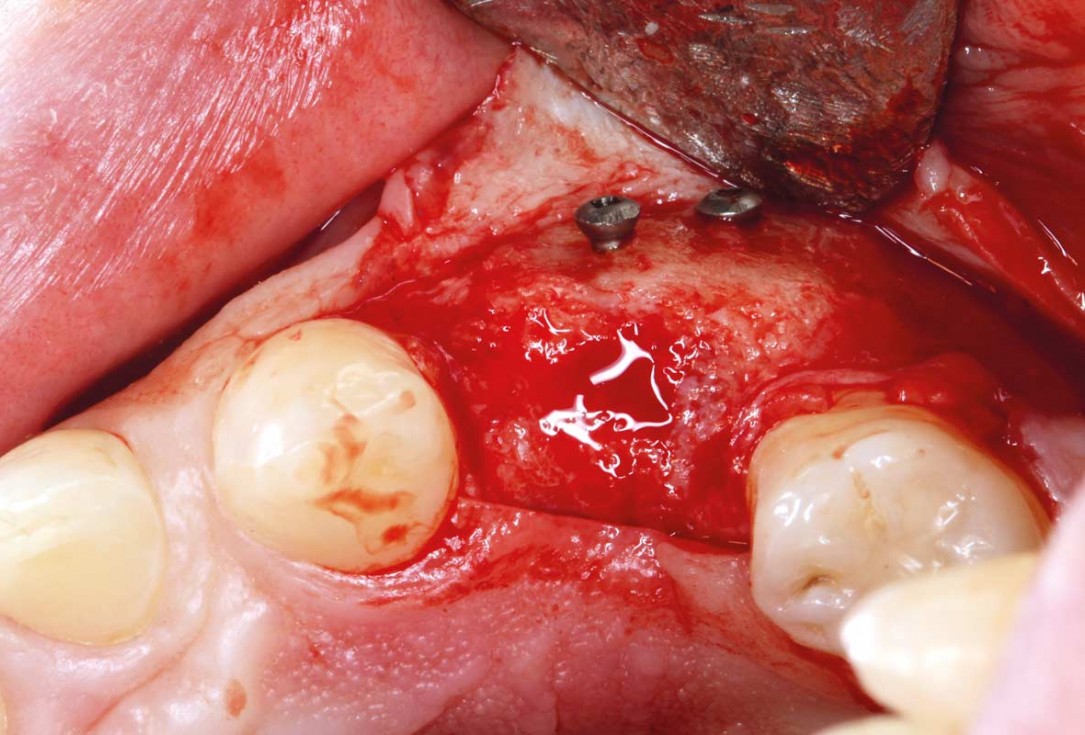

Full-thickness flap preparation bucally and lingually